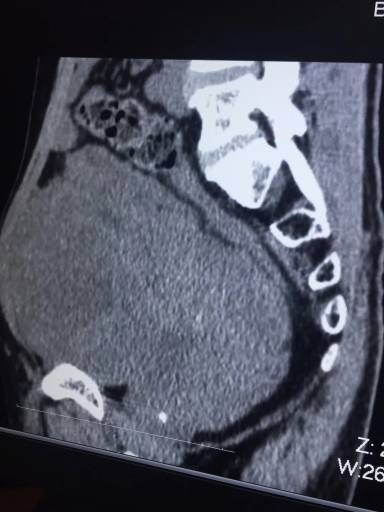

有一个自己多年的好朋友是中医科医生,把情况说给他听后他判断是尿道感染了,多喝水及开了一些中药服用,别说这个方法还真实管用,跑厕所的次数明显减少了。但吃了一阵子中药后情况又有反复,就继续在朋友那里开中药吃。半年前有天晚上发现自己的小腹有点突起,摸上去里面硬硬的,第二天赶紧去找他的朋友看,他的开诊所的中医朋友说可能是膀胱里面长了结石,只要坚持吃他开的中药一定能够消掉的,又吃了半年中药感到症状是有所好转,但小腹的突起继续在增大。因为陈叔身体比较瘦小,突起的小腹类似怀孕6个月的孕妇了。他的家人看到后很担心,催他一定要到大医院检查一下,到医院做了核磁共振后可是把他和家人都吓了一大跳,原来是小腹被一个巨大的肿瘤占据了,从片子上看盆腔内肿瘤占据的周围一点空隙也没有。

陈叔的核磁共振检查片

据阳西县人民医院技术总监、暨南大学附属第一医院普外科副主任医师高明医生介绍:在解剖学上,盆部是由盆腔腹膜包绕的部分(与腹腔相通)及盆腔腹膜外的部分(与腹膜后间隙相通)构成的。就是平时所说的“小肚子”。盆部原发性肿瘤起病往往很隐匿,通常病人经常因为症状不典型而延误就诊,有时候需要4~6 个月甚至 4~5 年之久才得到正确诊断,因此肿瘤有足够长的时间长的很大。陈叔切除的这个肿瘤长径有20多公分,可不把盆腔塞的满满的。